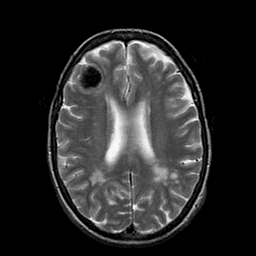

Metastatic Adenocarcinoma of the Colon: T2-weighted MR -- Slice #15

[Home][Help][Clinical] Slice 15